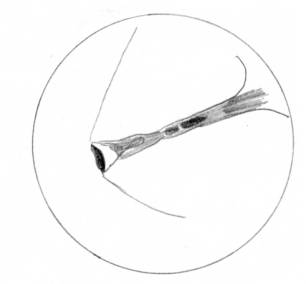

На рисунку 5а зображено

фотографію першого ребра досліджуваного

псевдотетрагонального фасеткового камінця. Гострокутна периферія в

цьому ребрі не чітко виражена. Тут видно заокруглення в бік 2-го кута. Поверхня концентрично зональна. На мою думку

це пояснюється найбільш інтенсивними

міжкамінцевими взаємодіями у точці

скопичення псевдотетрагонального камінця На схемі також помітно

заокруглення до 2-го кута.